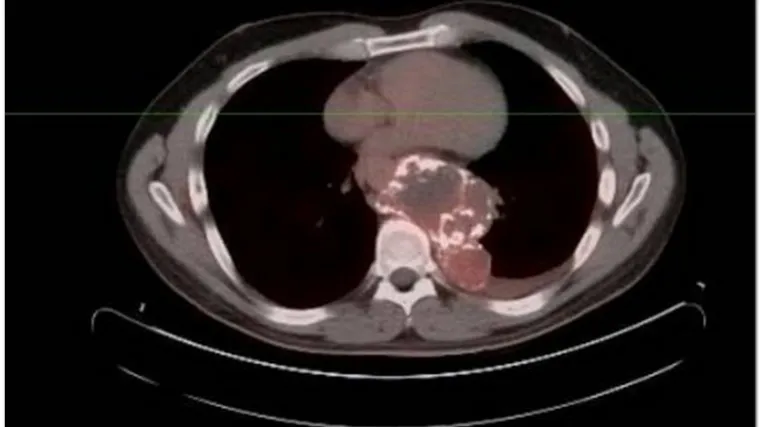

U Amerikancu rastao "tumor alien"

Osim neobičnog izgleda tumor je bio i kalcificiran te težak kao kamen. Operacija uklanjanja je trajala nekoliko sati.

SACRAMENTO - Kada se Josh Abken prije godinu dana požalio liječniku na stalnu bol u prsima poslan je na rendgen, a snimke su otkrile da u njemu raste tumor zapanjujućeg izgleda.

Dodatnim pretragama je utvrđeno da je tumor velik kao nogometna lopta, da je kalcificiran, odnosno da se oko njega stvorila koštana masa, a liječnici su pretpostavili da raste već desetak godina.

Tumor je već počeo pritiskati srce i pluća Josha Abkena pa su se liječnici odlučili na rizičnu i složenu operaciju.

Vađenje tumora je trajalo nekoliko sati, no bilo je uspješno.